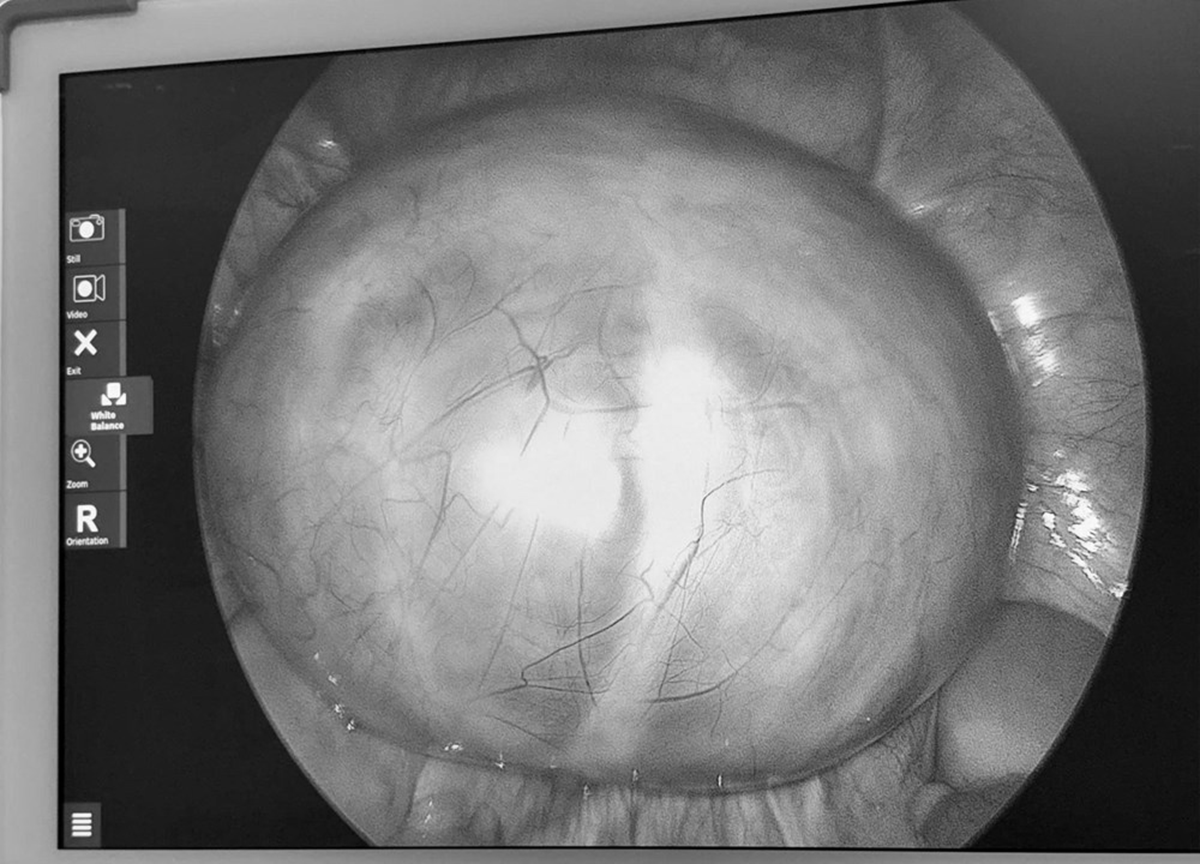

Tại viện qua siêu âm, các bác sĩ phát hiện buồng trứng trái có khối u lớn khoảng 14cm, cấu trúc nhiều vách. Sau hội chẩn, ê-kíp khoa Phụ sản đã tiến hành phẫu thuật vào ngày 3/4. Ca mổ diễn ra thuận lợi, khối u được bóc tách hoàn toàn, đồng thời bảo tồn tối đa chức năng sinh sản cho người bệnh.